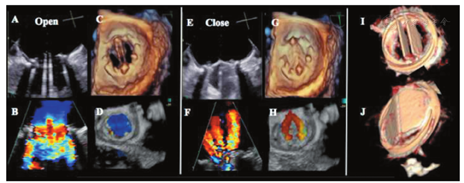

实时3D超声心动图,尤其是3D TOE检查对PHV的评价可提供比2D超声心电图更多的信息[22,23]。3D超声心动图面向瓣膜的外科切面对评价PHV功能非常有帮助,可识别反流束的存在、起源、方向及反流程度[11,24,25,26,27]。瓣周漏在3D超声上表现为缝合环外侧的回声失落,并可通过彩色多普勒进一步证实。3D超声可更好地显示PHV的结构如瓣叶、瓣环及其支撑结构。3D超声还用于评价血栓形成、血管翳及人工瓣膜开裂[28,29,30,31,32,33]。尤其当2D超声由于声影遮挡而造成图像质量差时,3D对于机械性二尖瓣及主动脉瓣的评价更具优势。2D超声不能显示的人工二尖瓣的心室面,通过3D超声可以显示[34]。

在经标准2D显像确定PHV最佳显示切面后,进行缩小扇角、3D放大和有或无彩色多普勒的全容积采集(心电图门控的单个心动周期或多个心动周期)。3D数据采集完成后,对图像任意切割以最优化显示心脏结构。通常将从LA面显示的二尖瓣图像旋转,使主动脉瓣位于12点位置、左心耳位于9点位置[11,26]。左、右冠状动脉窦之间的瓣叶联合处置于5点位置,而右冠窦与无冠窦之间的瓣叶联合处则置于8点位置。主动脉瓣瓣周漏常发生在右冠瓣与无冠瓣的交界区[35]。

笼-球型机械性瓣膜形同鸟笼状,显示球瓣在心室侧运动。2D超声显示金属支架为强回声,而球瓣近端表面回声稍弱。动态观察,阀体在笼内前后移动。二尖瓣位置的笼-球瓣,收缩期阀体定位在缝合环内。M超声显示笼、缝合环和球瓣分别呈现4种不同的回声。单叶侧倾碟瓣表现为单一回声在心室面呈前后运动。这种瓣叶相对于瓣环的开放角度在60°~80°,导致出现大小不同的两个瓣孔。M型超声显示瓣叶开放形成多向反射的强回声。双叶PHV显示为两片独立的碟瓣,二者几乎同步开放和关闭。瓣叶相对于瓣环的开放角度在75°~90°,开放的瓣膜包括三个瓣孔:一个较小的两瓣叶间的狭缝样的中央孔和两个较大的呈半圆形的侧孔(图2)。

生物瓣膜为三瓣叶结构,正常瓣叶为薄层结构(1~2 mm)呈非限制性运动,无脱垂征象。其2D和M型超声表现与自体瓣膜相似,在主动脉瓣位置收缩期和二尖瓣/三尖瓣位置舒张期呈盒状开放。其缝合环和立柱(图3短轴所示3个立柱)呈较强回声,影响了瓣叶的观察(图3A和图3B)。无支架主动脉生物瓣膜或同种异体主动脉瓣与自体主动脉瓣有相似的超声表现,但LV流出道和升主动脉的宽度增加。瓣膜植入后早期,无支架瓣膜插入部位会引起周围组织血肿和水肿。缝合线显示为PHV周围缝合环上的呈线样、较厚、较亮、多个均匀分布的静态结构。如果缝合线较松或较长则可呈一定动度。任何解剖部位的生物瓣膜其3D超声表现与自体主动脉瓣的表现类似,均为3个瓣叶,只不过在二尖瓣或三尖瓣位置植入的人工瓣膜直径较大,而在主动脉瓣或肺动脉瓣位置植入的瓣膜直径较小。

血流通过功能正常的PHV的血流特征不同于自体瓣膜。前向血流的特征因瓣膜位置、瓣孔的形状和数量不同而各异[7,14,83,84,85,97,98,99]。双重轮廓的多普勒频谱常见于机械性PHV中。PHV血流的多普勒频谱还包括由于阀体开启和关闭所产生的短暂、强回声、快速度的喀喇音信号(图4F,图5E)。在所有切面均应显示瓣孔被彩色血流完全充填(图2B)。

在单叶碟瓣,通常射流通过大的主孔(横截面呈半圆形射流)时产生浓密的较低速度血流,而射流通过小孔时呈暗淡的较高速度血流(依据立柱数量不同可为2~3束)。同样地,射流通过双叶机械性瓣膜的两个侧孔时产生浓密的低速血流,而通过中央孔产生暗淡的高速血流(图2F)。三股独立的射流构成前向跨瓣血流的特征性模式(图2B)。笼-球型PHV显示为血流沿整个球瓣周边通过,形成两个曲线状侧流并在中央部位形成涡流区。人工生物瓣膜前向血流模式为单一的中央性血流。

笼-球机械性瓣膜存在少量的正常反流(每搏2~6 ml的关闭流量)。单叶机械性瓣膜存在少量的生理性反流量(每搏5~9 ml),包括关闭流量和通过瓣叶周边孔隙的后向泄漏。在Medtronic Hall瓣膜中,也常测及围绕中央立柱的少量反流。双叶机械性瓣膜一般有少量的正常反流(每搏5~10 ml)。在多普勒彩色血流成像上,经常发现起源于碟瓣枢纽点的两股主反流束变成一个或多个"羽毛"样和一个较小的中央性射流(图2G,图2I)。亦可测及围绕瓣叶关闭缘的小反流束。少量的中央性(在对合点或接近交界处)反流(<1 ml)也常常见于人工生物瓣膜,而在牛心包瓣膜中更为常见。无支架瓣膜,包括同种异体和自体移植瓣膜,比支架型瓣膜更常出现少量的瓣膜反流。